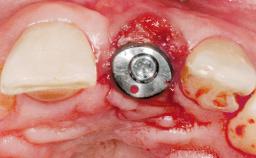

A 30-year-old female patient was referred to the office for the treatment of tooth 11. Her chief concern at the initial visit was to inquire, “Why is my tooth pink?” Upon clinical examination, it was determined that tooth 11 had a previous history of trauma and that the clinical crown had become noticeably pink in color as a result of internal resorption. This diagnosis was confirmed radiographically, indicating a large radiolucency involving the central and distal portions of the clinical crown. It was determined that restoration of this tooth was not possible, and that extraction was indicated. The presence of a mid-line diastema, which the patient wanted to reproduce, directed the treatment plan for tooth replacement utilizing a dental implant.

Type of Implants One-Piece|Reduced-Diameter

Attachment One-Piece|Reduced-Diameter

Placement Protocol Immediate implant placement

Tooth Site Maxillary incisor or canine

Socket Morphology Single-root socket

Socket Integrity Sufficient, with intact bone walls

Bone Volume Sufficient, with intact walls